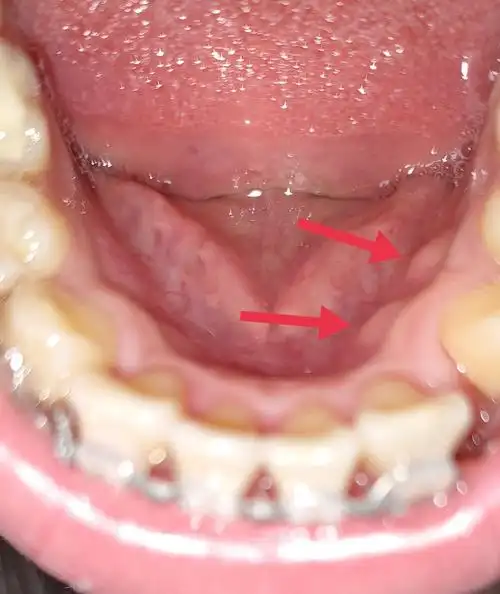

牙龈增生

【求助】这是齿龈增生吗,怎么治疗

这是牙骨增生吗

牙槽骨增生放任不管会一直长吗怎么治疗